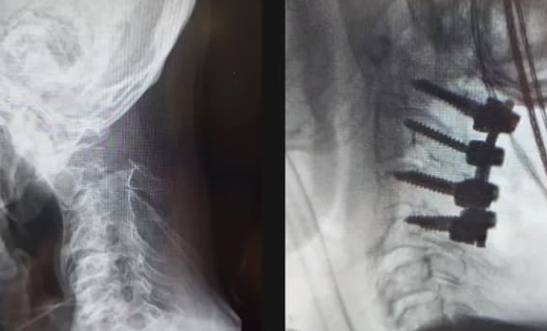

後方より椎間板の間に補強材(ケージと呼ばれています)を入れて、医療用のネジ(スクリュー)で固定して、安定させる方法です。